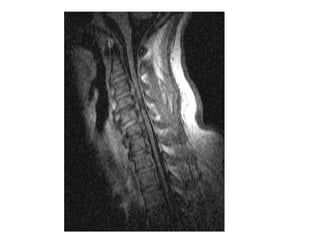

Surgical management for cervical  spondylotic myelopathy:  Early results in Abuja Biodun Ogungbo MBBS, FRCS, FRCS (SN), MSc

Background  Cervical spondylotic myelopathy (CSM) is a common cause of spinal dysfunction in the elderly.  It appears to occur in a much younger age group in Nigeria.  However it is frequently not diagnosed early due to the paucity of MRI scans. When diagnosed, many are treated with  steroids  and conservatively. Therefore, patients present late for surgical intervention.

Objectives We present a review of patients with cervical spondylotic myelopathy.  The early results of surgical management in 6 patients are presented to highlight the safety of operative intervention.

Results  Six patients have undergone surgical management for CSM since August 2009.  Five of the patients were quadriplegic at the time of the operation.  They were unable to feed themselves or perform activities of daily living without assistance.

Results   Three patients underwent anterior cervical discectomy and fusion and 3 had cervical laminectomy performed.  Five patients improved significantly post operatively with sustained neurological improvement over 6 months of the operation.  There was one death due to pulmonary embolism 3 weeks after surgery.

Surgical management forcervical spondylotic myelopathy: Early results in Abuja Biodun Ogungbo MBBS, FRCS, FRCS (SN), MSc

Background Cervicalspondylotic myelopathy (CSM) is a common cause of spinal dysfunction in the elderly. It appears to occur in a much younger age group in Nigeria. However it is frequently not diagnosed early due to the paucity of MRI scans. When diagnosed, many are treated with steroids and conservatively. Therefore, patients present late for surgical intervention.

Objectives We presenta review of patients with cervical spondylotic myelopathy. The early results of surgical management in 6 patients are presented to highlight the safety of operative intervention.

Results Sixpatients have undergone surgical management for CSM since August 2009. Five of the patients were quadriplegic at the time of the operation. They were unable to feed themselves or perform activities of daily living without assistance.